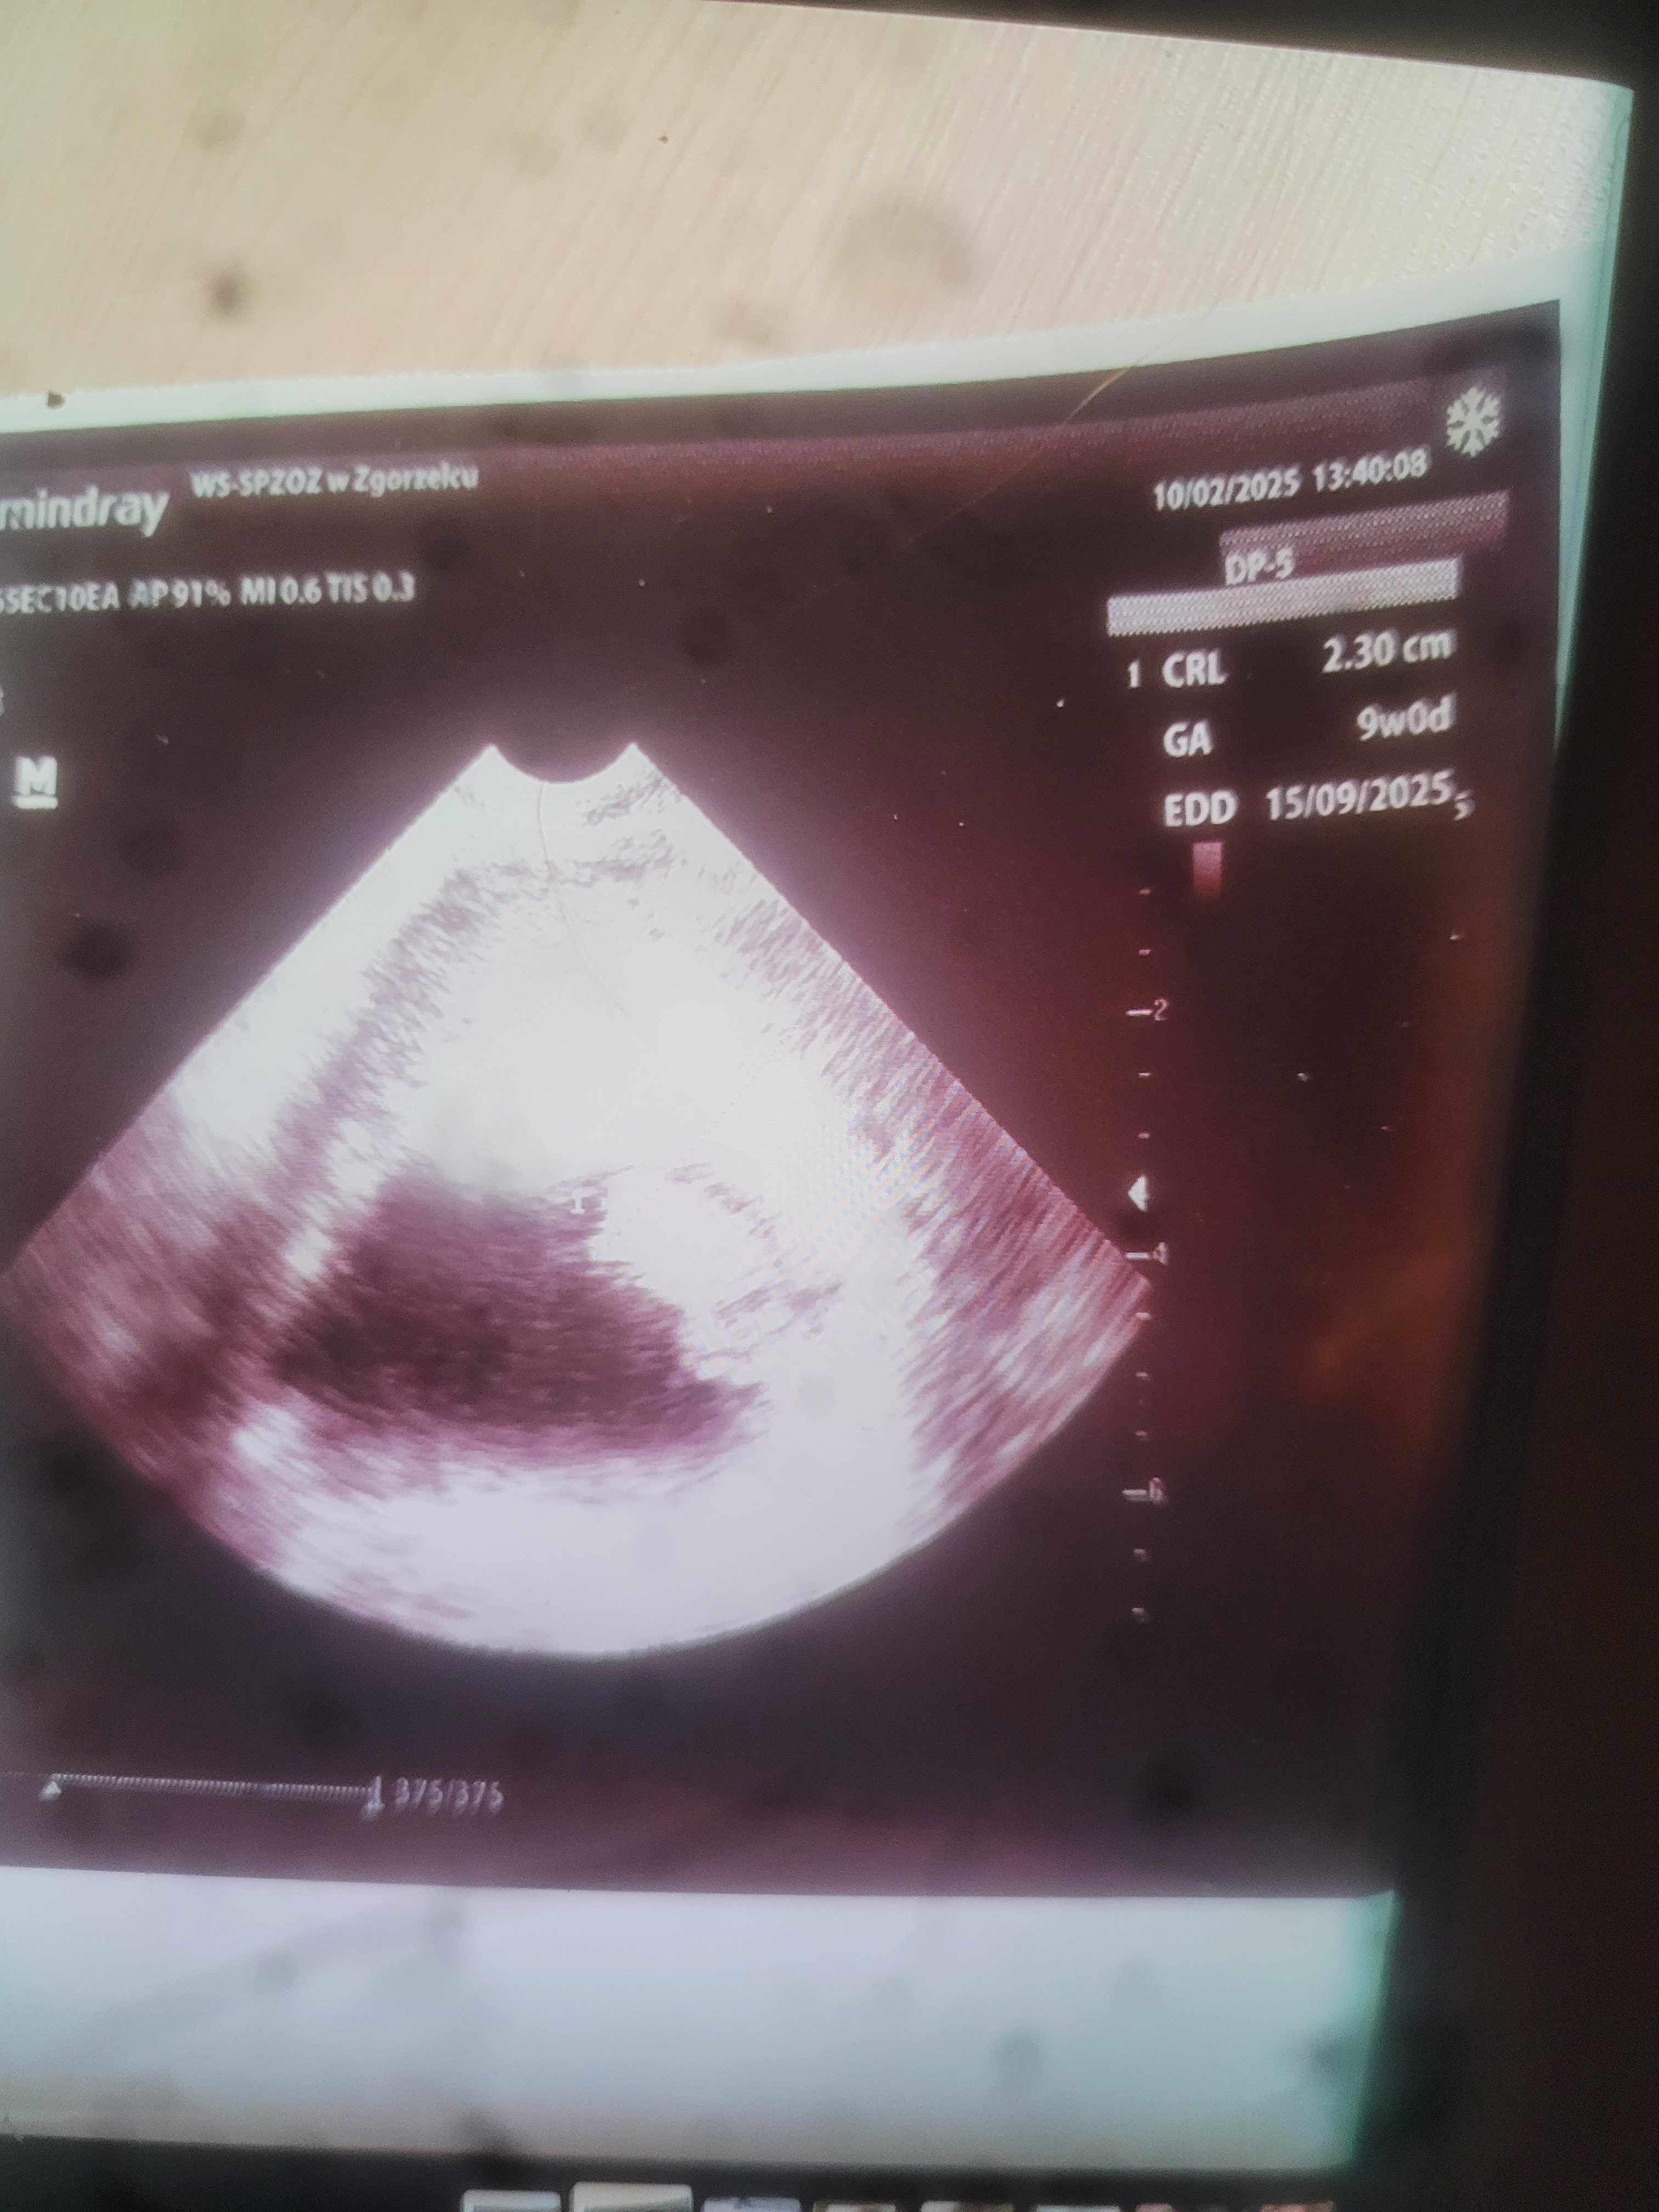

Mam tylko takie zdjęcie nie dostałam wydruku robiłam telefonem żelek ma 2.30 cm wbrew co było pisane jak pytałam że bić z tego nie będzie ma się dobrze serduszko bije. Termin na 15 września przesunięty. 9 tc